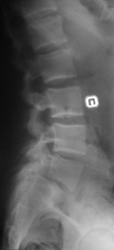

Молодой человек, занимаясь в спортзале, неаккуратно взял вес. Беспокоят боли в пояснице.

Истинный передний спондилолистез I степени и незаращение дужки L5

+1. Spina bifida S1.

На мой взгляд, сложно сказать явился ли листез следствием травмы (гипернагрузки), предыдущих снимков скорее всего нет. но исходя из умозаключения "где тонко, там и рвётся", смею предположить, что причина жалоб пациента находится именно на уровне спондилолистеза. ...правда, как облачить это в форму заключения протокола рентгенографического исследования я не знаю...

Если бы такой листез был следствием однократной гипернагрузки, думаю, что без инвалидной коляски бы не обошлось. Но о дальнейшем занятии таким спортом нужно задуматься.